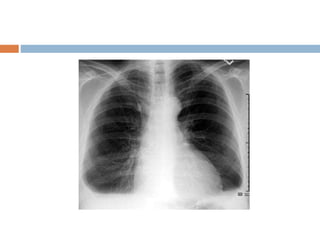

Massive pleural effusion

 Opacification of entire hemithorax and shifting

of mediastinum to opposite side

 If the effusion crosses 2nd rib anterior border it

is said to be massive

 If it crosses 4th rib it is said to be moderate

 Below 4th rib is mild